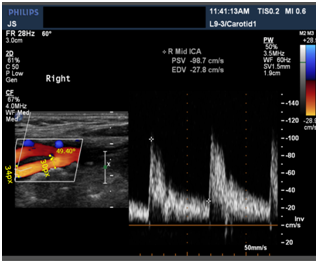

Input dicom images

In the demo version of Sante Dicom Viewer we can measure the radius only in pixels. To convert that to centimeters, calibration length of the image is considered and correspondingly a conversion factor is multiplied to get diameter in centimeters.

CL: Calibration length, which is 7cm in the image below.

Figure 4 Ultrasound image of Internal Carotid Artery.

365 is the measured length of the rectangle in pixels where the blood vessel is shown in ultrasound image (Figures 4-6).

Diameter(D)= 3.0*55 365*2 MathType@MTEF@5@5@+= feaagKart1ev2aaatCvAUfeBSjuyZL2yd9gzLbvyNv2CaerbuLwBLn hiov2DGi1BTfMBaeXatLxBI9gBaerbd9wDYLwzYbItLDharqqtubsr 4rNCHbGeaGqk0di9crFfpeea0xh9v8qiW7rqqrFfpeea0xe9Lq=Jc9 vqaqpepm0xbba9pwe9Q8fs0=yqaqpepae9pg0FirpepeKkFr0xfr=x fr=xb9adbaqaaeGaciGaaiaabeqaamaabaabaaGcbaqcLbsacaWGeb GaamyAaiaadggacaWGTbGaamyzaiaadshacaWGLbGaamOCaiaacIca caWGebGaaiykaiabg2da9OWaaSaaaeaajugibiaaiodacaGGUaGaaG imaKqzadGaaiOkaKqzGeGaaGynaiaaiwdaaOqaaKqzGeGaaG4maiaa iAdacaaI1aqcLbmacaGGQaqcLbsacaaIYaaaaaaa@4FF2@ cm=0.220602cm

After getting the input velocity (PSV) from the dicom images, we convert it to flow rate from the formula4 and as the current flows through the above circuit, flow rate at each segment is calculated and converted back to velocities to get the blood flow velocities. Similar to the above ultrasound image, 5 images at different points in CCA, ICA, and ECA respectively of the same patient were taken. And velocities at the points L2, L5 and L3 were calculated given velocities at L1 and L4 with ±5% errors based on the flow rate division with different Windkessel models stitched along the artery with the calculated radius from the images and assuming an average elasticity, thickness, viscosities and densities of the blood Figure 7.